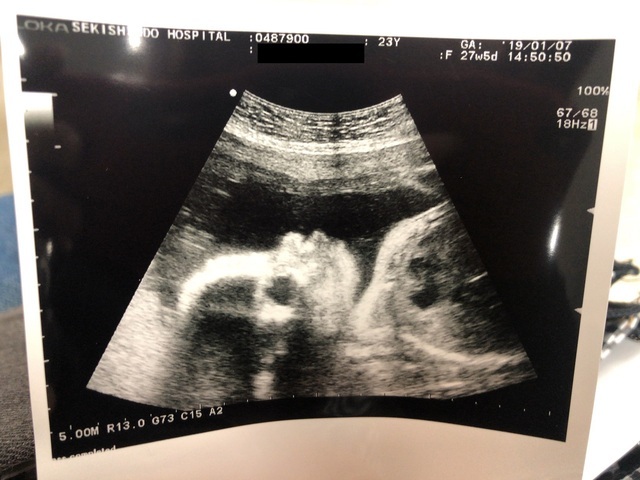

27週2日(27w2d・男の子)|こよ さん(30歳)

エコー写真撮影時のエピソード:

長く管理入院していました。

入院中に撮ってもらったエコー写真です。

ずっと恥ずかしがり屋さんだったので16wから27wまで顔は見せてもらえませんでした!

やっと27wの時に見せてくれた顔は主人にそっくり!

びっくりしましたw

今でもハッキリ覚えています!!